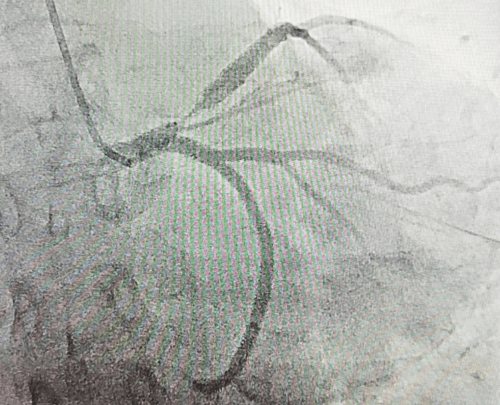

51歲的郭女士,因反復(fù)胸痛3天,加重2小時(shí)入院,入院后胸痛癥狀反復(fù)發(fā)作,檢查心電圖提示前壁導(dǎo)聯(lián)ST段明顯壓低,在此危急時(shí)刻心九科值班醫(yī)生陶醫(yī)生立即啟動(dòng)導(dǎo)管室,心九科介入團(tuán)隊(duì)行冠脈造影提示患者前降支近段99%狹窄,患者病情危在旦夕,遂立即行支架植入術(shù)解除冠脈狹窄,患者生命得以及時(shí)救治。

冠脈手術(shù)后